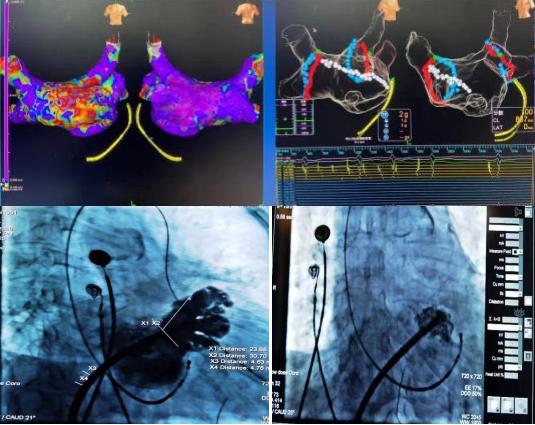

2020年12月30日,延安大學(xué)咸陽醫(yī)院心血管內(nèi)七病區(qū)成功開展一例射頻消融+左心耳封堵一站式介入手術(shù)。該種微創(chuàng)手術(shù)既可以解決患者房顫癥狀問題,又能預(yù)防房顫腦卒中的風(fēng)險,將卒中和出血風(fēng)險降到最低。一消一封,兩種手術(shù),一站結(jié)合,一勞永逸。

78歲高齡的杜奶奶,受到房顫疾病困擾多年,從寶雞慕名來到我院。經(jīng)我科高勝利主任、賀新榮責(zé)任總醫(yī)師及徐云鵬主治醫(yī)生的詳細(xì)檢查與謹(jǐn)慎的決策,同時在心血管病院吳棟梁院長、張玉順教授和電生理同仁的協(xié)助下,成功地進(jìn)行了一站式手術(shù)。該手術(shù)分兩部分進(jìn)行,首先是行房顫射頻消融術(shù):房顫射頻消融手術(shù)可最大限度地使患者恢復(fù)竇性心律(正常心律);第二部分是行左心耳封堵術(shù):左心耳封堵術(shù)是目前全球預(yù)防房顫患者卒中的治療新趨勢,它能有效減少病人的病死率、致殘率,同時減少出血的發(fā)生。兩種手術(shù)一站式結(jié)合,“一消一封”,“一勞永逸”。手術(shù)過程順利,術(shù)后患者轉(zhuǎn)復(fù)為竇性心律,左心耳封堵傘完全展開,造影顯示無殘余分流。患者各項(xiàng)生命體征平穩(wěn),順利返回病房。在主管護(hù)師趙燕子的全程指導(dǎo)下,護(hù)理團(tuán)隊(duì)從患者臥位-飲食-運(yùn)動-心理進(jìn)行全方位的護(hù)理。新年的第4天,杜奶奶恢復(fù)情況良好,順利出院。她笑著說:“我好了,我好了,太謝謝你們了”!